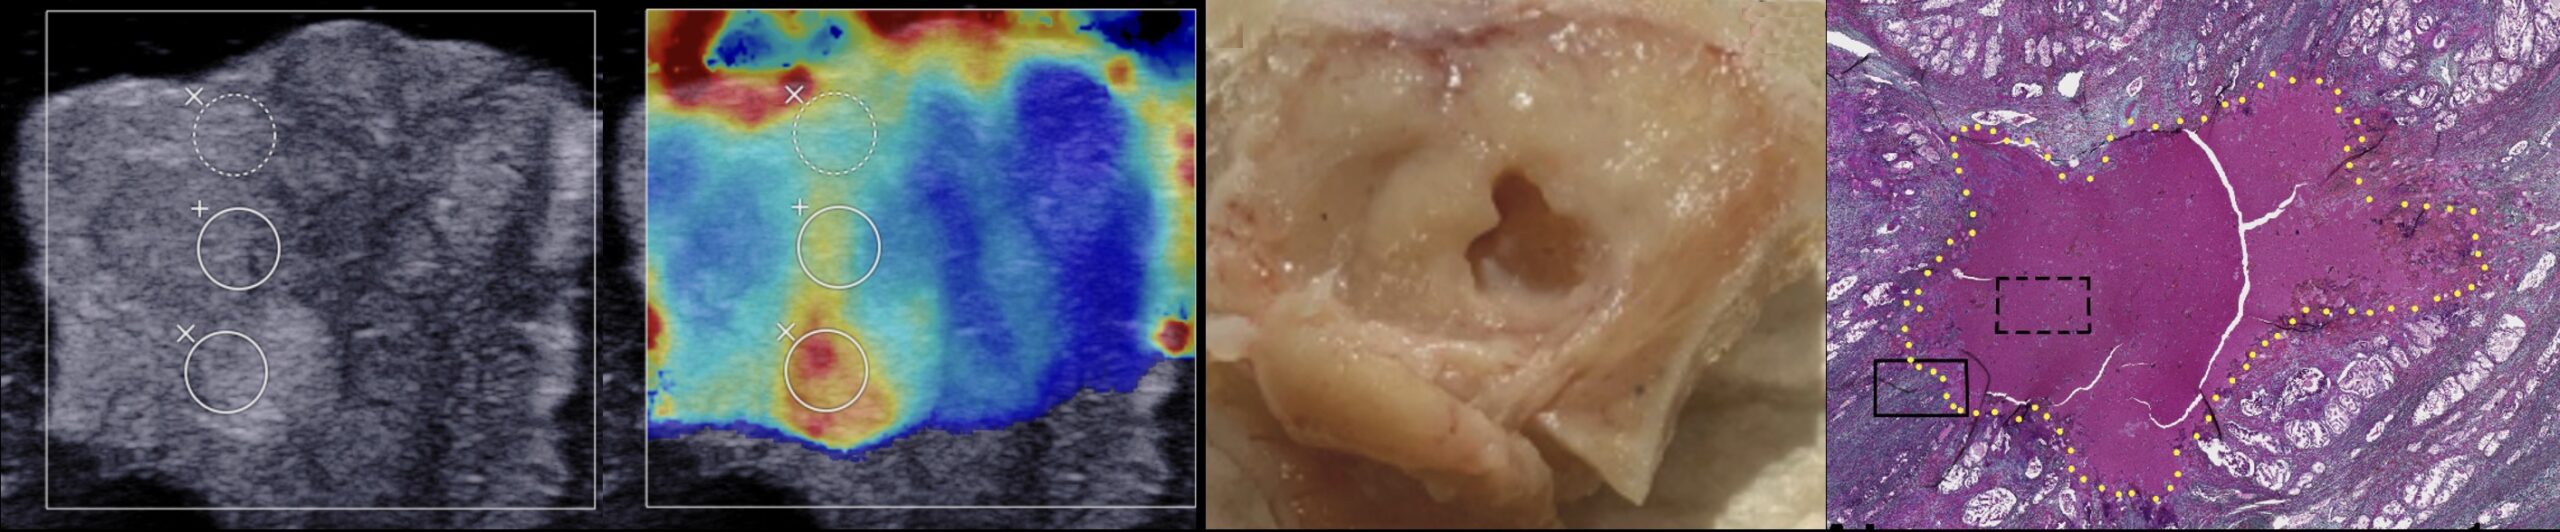

Недавно нами была продемонстрирована принципиальная возможность механического разрушения тканей предстательной железы человека ex vivo методом гистотрипсии с кипением, при этом ткань в области воздействия была ликвифицирована до субклеточных фрагментов, что было подтверждено гистологически и методами электронной микроскопии. Репрезентативность механических свойств данной выборки была подтверждена при помощи диагностической процедуры эластографии на основе сдвиговых волн.

Также недавно мы впервые экспериментально показали возможность получения локализованных механических разрушений в ткани злокачественной опухоли предстательной железы человека ex vivo.

На данный момент в Лаборатории ведутся исследования на большей выборке препаратов для изучения отклика различных опухолей предстательной железы на механическое разрушение методом гистотрипсии с кипением, влияния их упругих свойств на этот отклик, а также для определения диапазона оптимальных параметров воздействия для эффективного и быстрого разрушения различных новообразований предстательной железы.